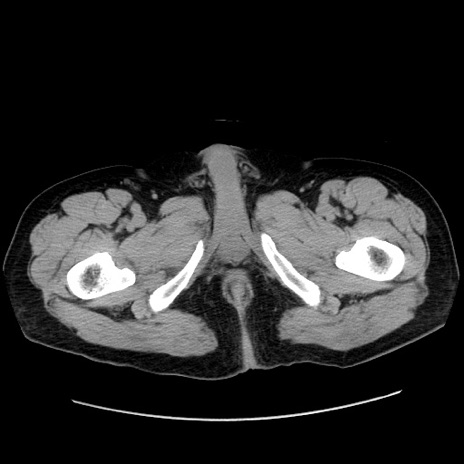

症例30(横断像)

【症例】80歳代男性

【主訴】臍周囲痛

【現病歴】約6時間前から臍下部痛が出現。次第に腹部膨隆・背部痛も生じてきたため来院。背部痛の場所は変化しない。

【身体所見】意識清明、BT 36.3℃、BP  131/87mmHg、P 87bpm、SpO2 100%(RA)、臍周囲自発痛・圧痛あり、反跳痛なし、自発痛部位に一致して板状硬あり、腹部膨隆、腸雑音減弱、CVA tenderness両側陰性。